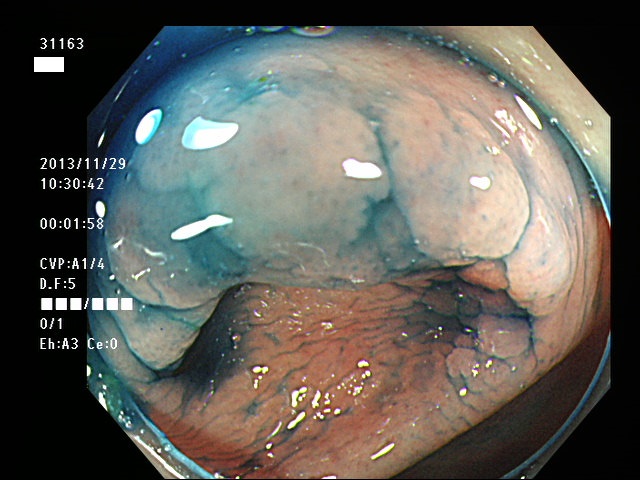

虫垂開口部の過形成ポリープ(SSAP)の例

一般に虫垂過形成ポリープが見られる方は「大腸の他の部位にもポリープ(特にSSAP)が見つかる可能性が非常に高い」のです。つまり「危険な腸である」という警告灯になるのです。虫垂は大腸の一番奥ですから「観察のスタート地点」です。ここで警告灯が出ることは非常に有益な訳です。